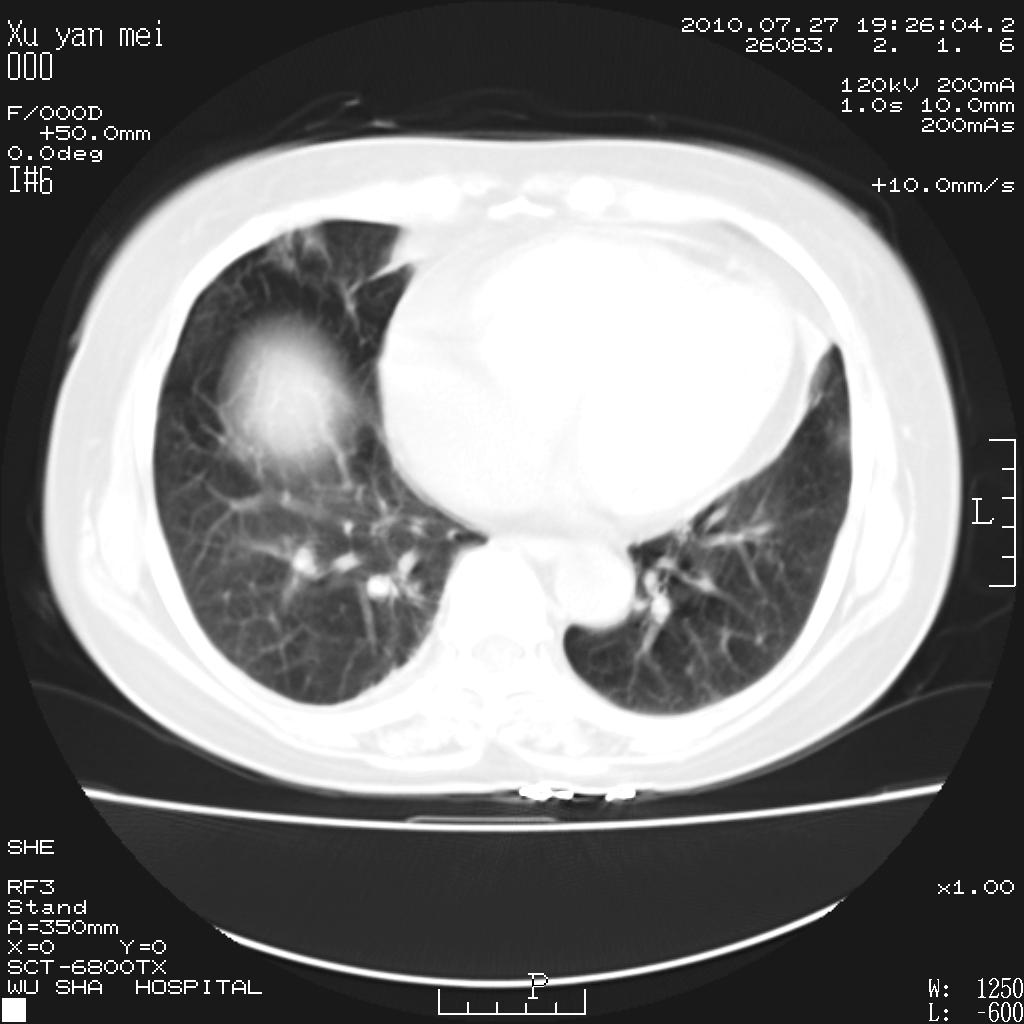

女,60岁,胸痛就诊,右肺结核?炎症?其它?(胸片右侧中上肺野确实看不到什么啊)

1)考虑两肺感染性病变;建议抗炎治疗后复查。2)双侧少量胸腔积液。

1)考虑两肺感染性病变;建议抗炎治疗后复查。2)右侧少量胸腔积液。

双肺炎症可能性大,建议抗炎后复查。右侧胸腔少量积液。双侧胸膜轻度增厚。

考虑两肺感染性病变;不除外肺栓;建议抗炎治疗后复查。